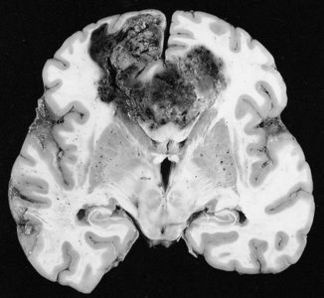

Glioblastoma (GB) is the most common intracranial malignancy with an annual incidence of approximately 3 C 5 cases per 100,000 individuals. In terms of overall cancer burden GB is uncommon, however, the combination of brain localization, invasiveness, and extremely poor prognosis make it one of the most feared of all cancer diagnosis. Glioblastoma currently has an overall median survival time of 12 C 15 months despite maximally combined therapy of neurosurgery, radiation, and combination thermotherapy. It is interesting to note that the extremely slow development of effective therapy/treatment lies in stark contrast to the rapidly expanding foundation of knowledge regarding the molecular pathogenesis of this disease. The vast majority of research in the field of neuro-oncology has been published in the last 20-30 years, largely driven by a greater understanding of brain tumor genetics. More recent molecular classification has provided the basis for the existence of four distinct types of high-grade primary glioblastoma: classical, mesenchymal, neural, and pro-neural subtypes. These subtypes are differentiated molecularly based upon various proteomic features, signature mutations, methylation features, and currently identified tranional regulators. The comprehensive molecular classification of high-grade gliomas is just now starting to transform current classification, which currently follows the consensus WHO histopathological criteria. Despite sophisticated molecular classification schemes, a relatively high percentage of gliomas remain difficult to reproducibly categorize due to considerable histological overlap. Phenotypically, the tumor displays marked hypercellularity, serpiginous areas of necrosis, and expansive endothelial cell proliferation with tumor vasculature being torturous, disorganized, and highly permeable. Grade IV neoplasms exhibit extremely aggressive proliferation of endothelial cells as compared to Grade II and Grade III tumors. The increased vascular permeability compounds the issue by leading to increased cerebral edema and inflammation. Abnormalities in the endothelial walls, pericyte coverage, and basement membrane also result in loss of structure and function of the critical blood brain barrier.